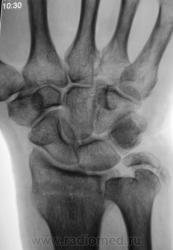

Пациент направлен на рентгенографию лучезапястного сустава.

Пациент направлен на рентгенографию лучезапястного сустава хирургом, была травма. После производства снимков стали допытываться у пациента, о "факте более ранней травмы". Все бесполезно - не помнит, не знает ....

Ваше мнение, уважаемые коллеги?